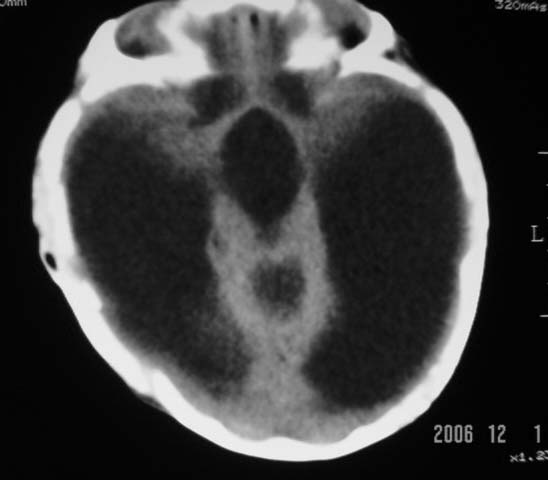

3m,出生时有新生儿吸入性肺炎、hie、化脓性脑膜炎,近一个月发现头围增大(51cm),无恶心呕吐。

3m,出生时有新生儿吸入性肺炎、hie、化脓性脑膜炎,近一个月发现头围增大(51cm),无恶心呕吐,脑室系统全程扩张,脑皮质变薄,结合病史考虑交通性脑积水

3m,出生时有新生儿吸入性肺炎、hie、化脓性脑膜炎,近一个月发现头围增大(51cm),无恶心呕吐,脑室系统全程扩张,脑皮质变薄,结合病史考虑重度交通性脑积水。